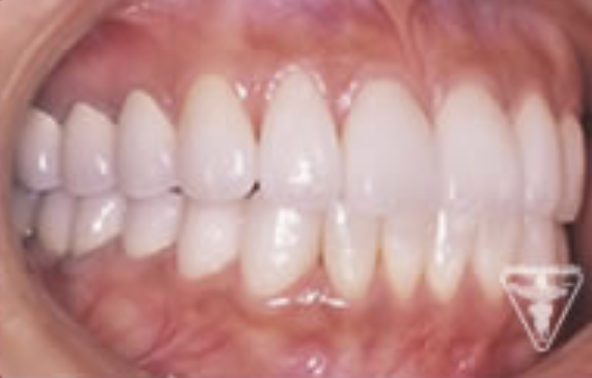

治療後

顎のずれを改善し、上下のかみ合わせの関係を理想的にして筋肉や関節の緊張が取れ、穏やかな表情に変られました。「良く噛めるようになった。」と評価をいただきました。